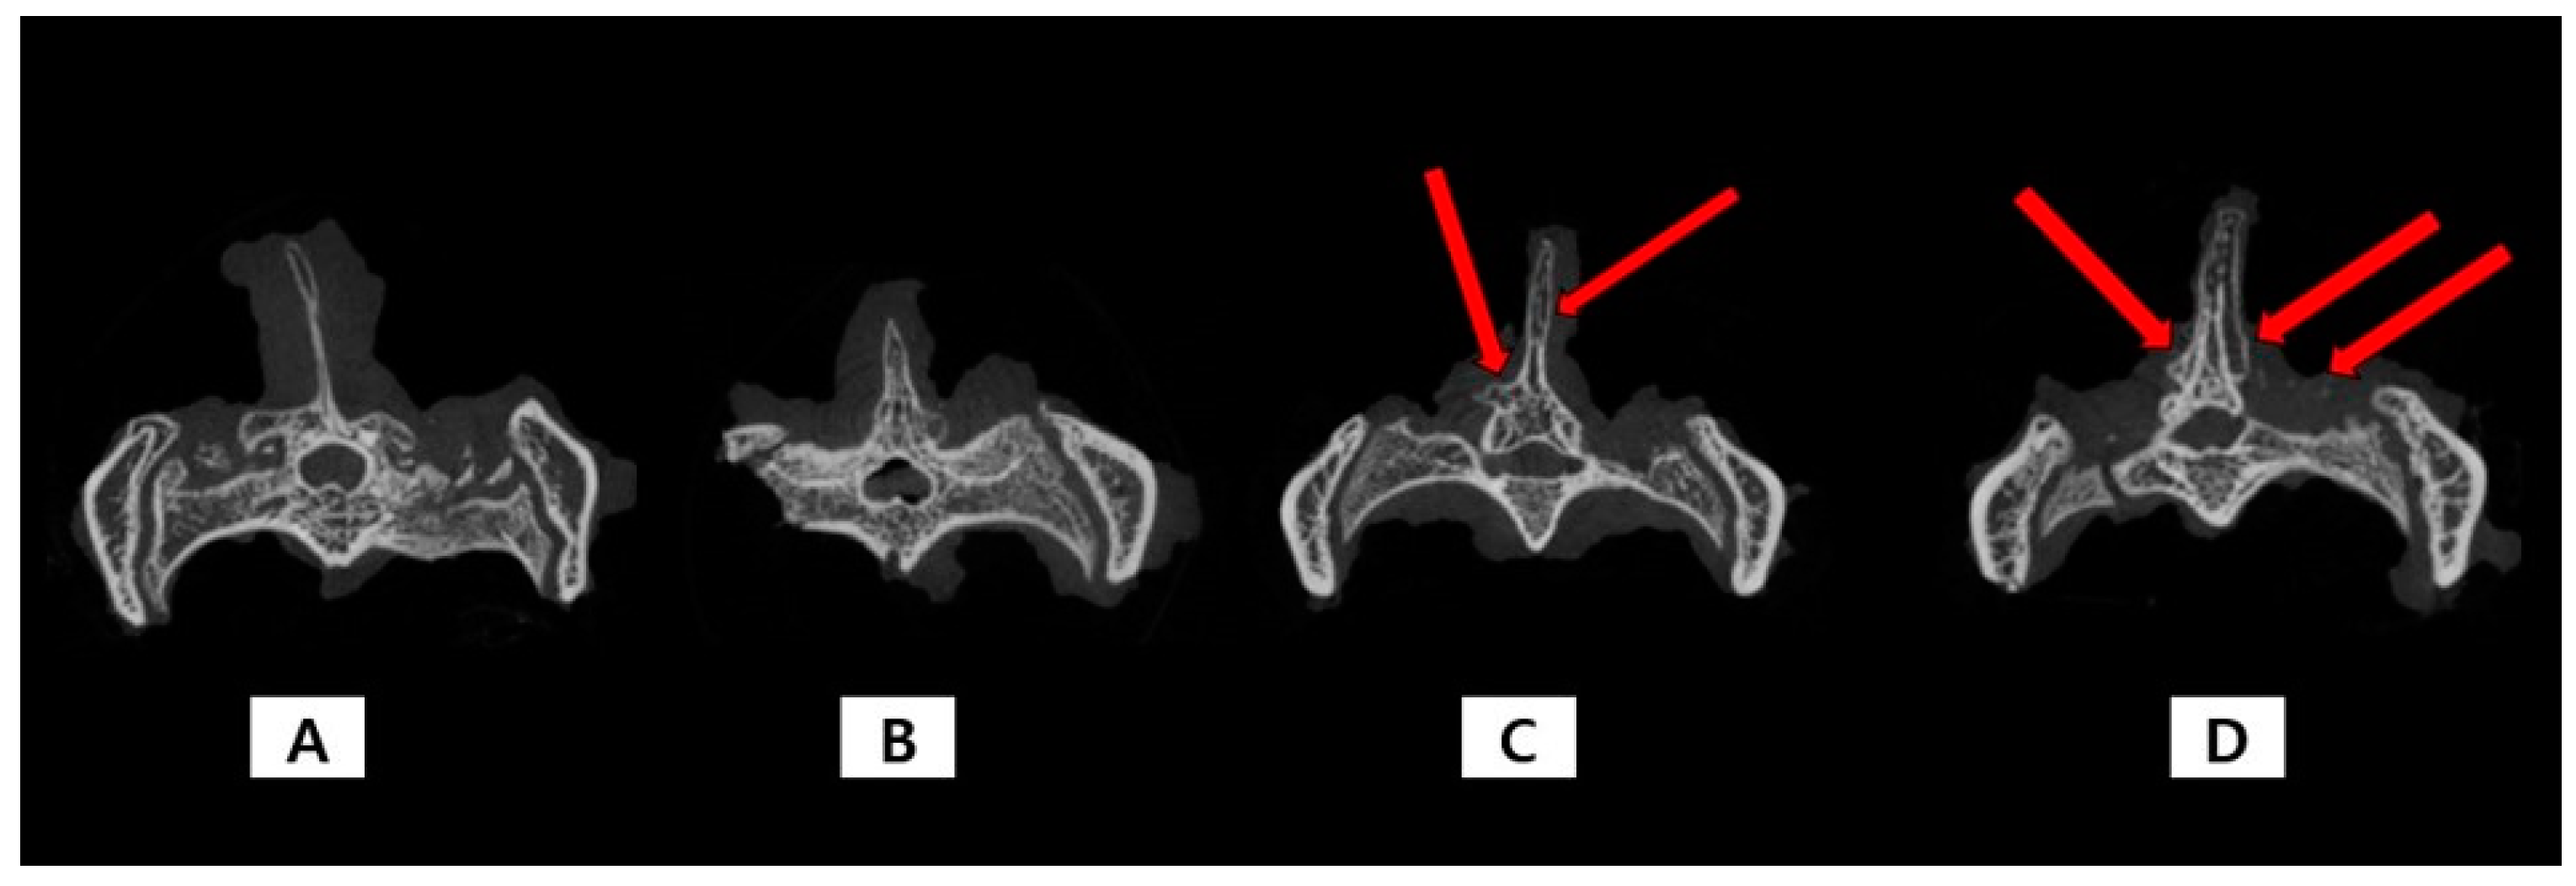

2.2. Micro-CT

| Defect Group (n = 6) | MSN Group (n = 8) | TA-MSN-LF Low Group (n = 8) | TA-MSN-LF High Group (n = 8) | p | |

| Bone volume (mm3) | 84.761 ± 8.507 | 99.697 ± 14.234 | 114.701 ± 15.703 | 121.335 ± 4.204 | <0.05 * |

| Trabecular thickness (mm) | 0.485 ± 0.058 | 0.400 ± 0.029 | 0.416 ± 0.046 | 0.412 ± 0.047 | 0.348 |

| Trabecular number (1/mm) | 0.152 ± 0.022 | 0.179 ± 0.030 | 0.211 ± 0.015 | 0.212 ± 0.020 | <0.05 * |

| Trabecular separation (mm) | 4.500 ± 0.343 | 4.409 ± 0.246 | 4.277 ± 0.238 | 4.307 ± 0.425 | 0.637 |